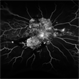

- Proliferative Diabetic retinopathy, Diabetes

- Proliferative Diabetic Retinopathy